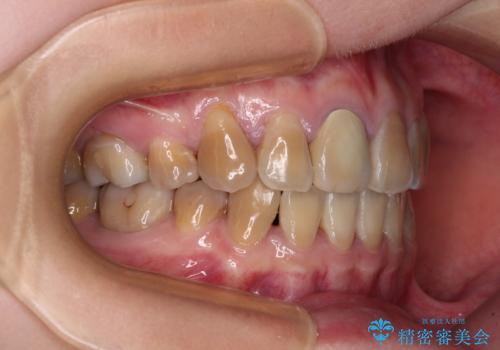

上下の正中がずれていましたが、抜歯矯正であったので、極力正中位置を合わせるように治療を進めて行きました。

顎間ゴムの使用などにより、正中位置を改善することができました。